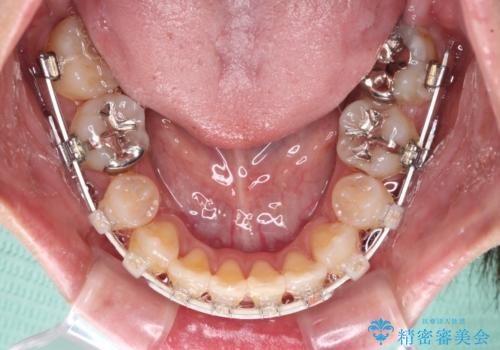

気になる八重歯を目立たない装置で改善 ハーフリンガル矯正

- ハーフリンガル

目立たない装置を希望されたので、上顎が裏側装置のハーフリンガルを選択し、上下左右の小臼歯(計4歯)を抜歯して矯正治療を行うこととしました。

補助装置を併用することで、八重歯を速やかに改善し、治療期間の短縮を図ることとしました。